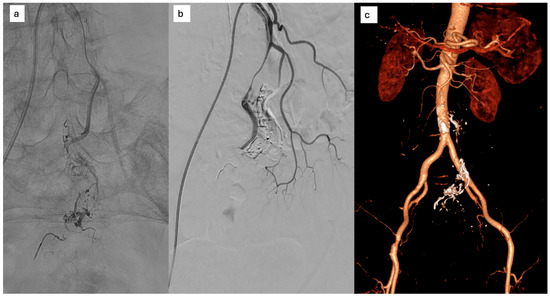

Background/Objectives: Endoscopic biliary stenting is the standard palliative intervention for malignant biliary obstruction, aimed at restoring ductal patency. Radiofrequency ablation (RFA) has been introduced as an adjunct technique to improve stent durability and patient outcomes. However, the literature remains inconclusive regarding which patients are most likely to benefit from the combination of RFA and stenting. Methods: We retrospectively described clinical outcomes of 24 patients undergoing endobiliary RFA combined with biliary stenting for malignant biliary obstruction. Post-procedural and 6-month outcomes were assessed using technical success and changes in serum bilirubin; procedure-related adverse events were extracted from available medical records. Results: Nineteen females and five males were included in the study. The most prevalent diagnoses were metastatic adenocarcinoma (n = 8) and cholangiocarcinoma (n = 6). 25% of patients did not complete the 6-month follow-up due to malignancy progression. 16 out of 18 maintained the patency of biliary stents. Repeat endoscopic intervention for suspected stent dysfunction was documented in one patient. When analyzed in an intention-to-treat manner (counting deaths before 6 months as failures), the corresponding 6-month patency/clinical success rate was 16/24 (66.7%). Conclusions: In this retrospective single-center experience, RFA combined with biliary stenting was feasible and was associated with maintained biliary drainage in a majority of patients who survived to the 6-month assessment.